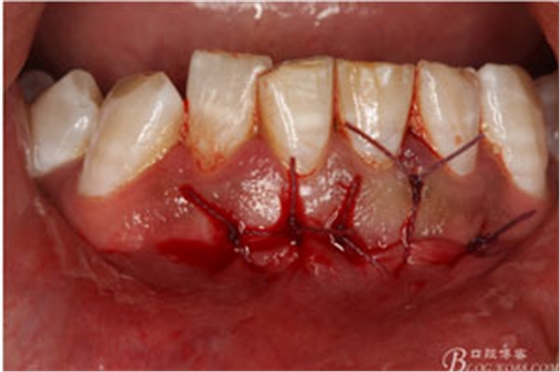

圖17.縫合